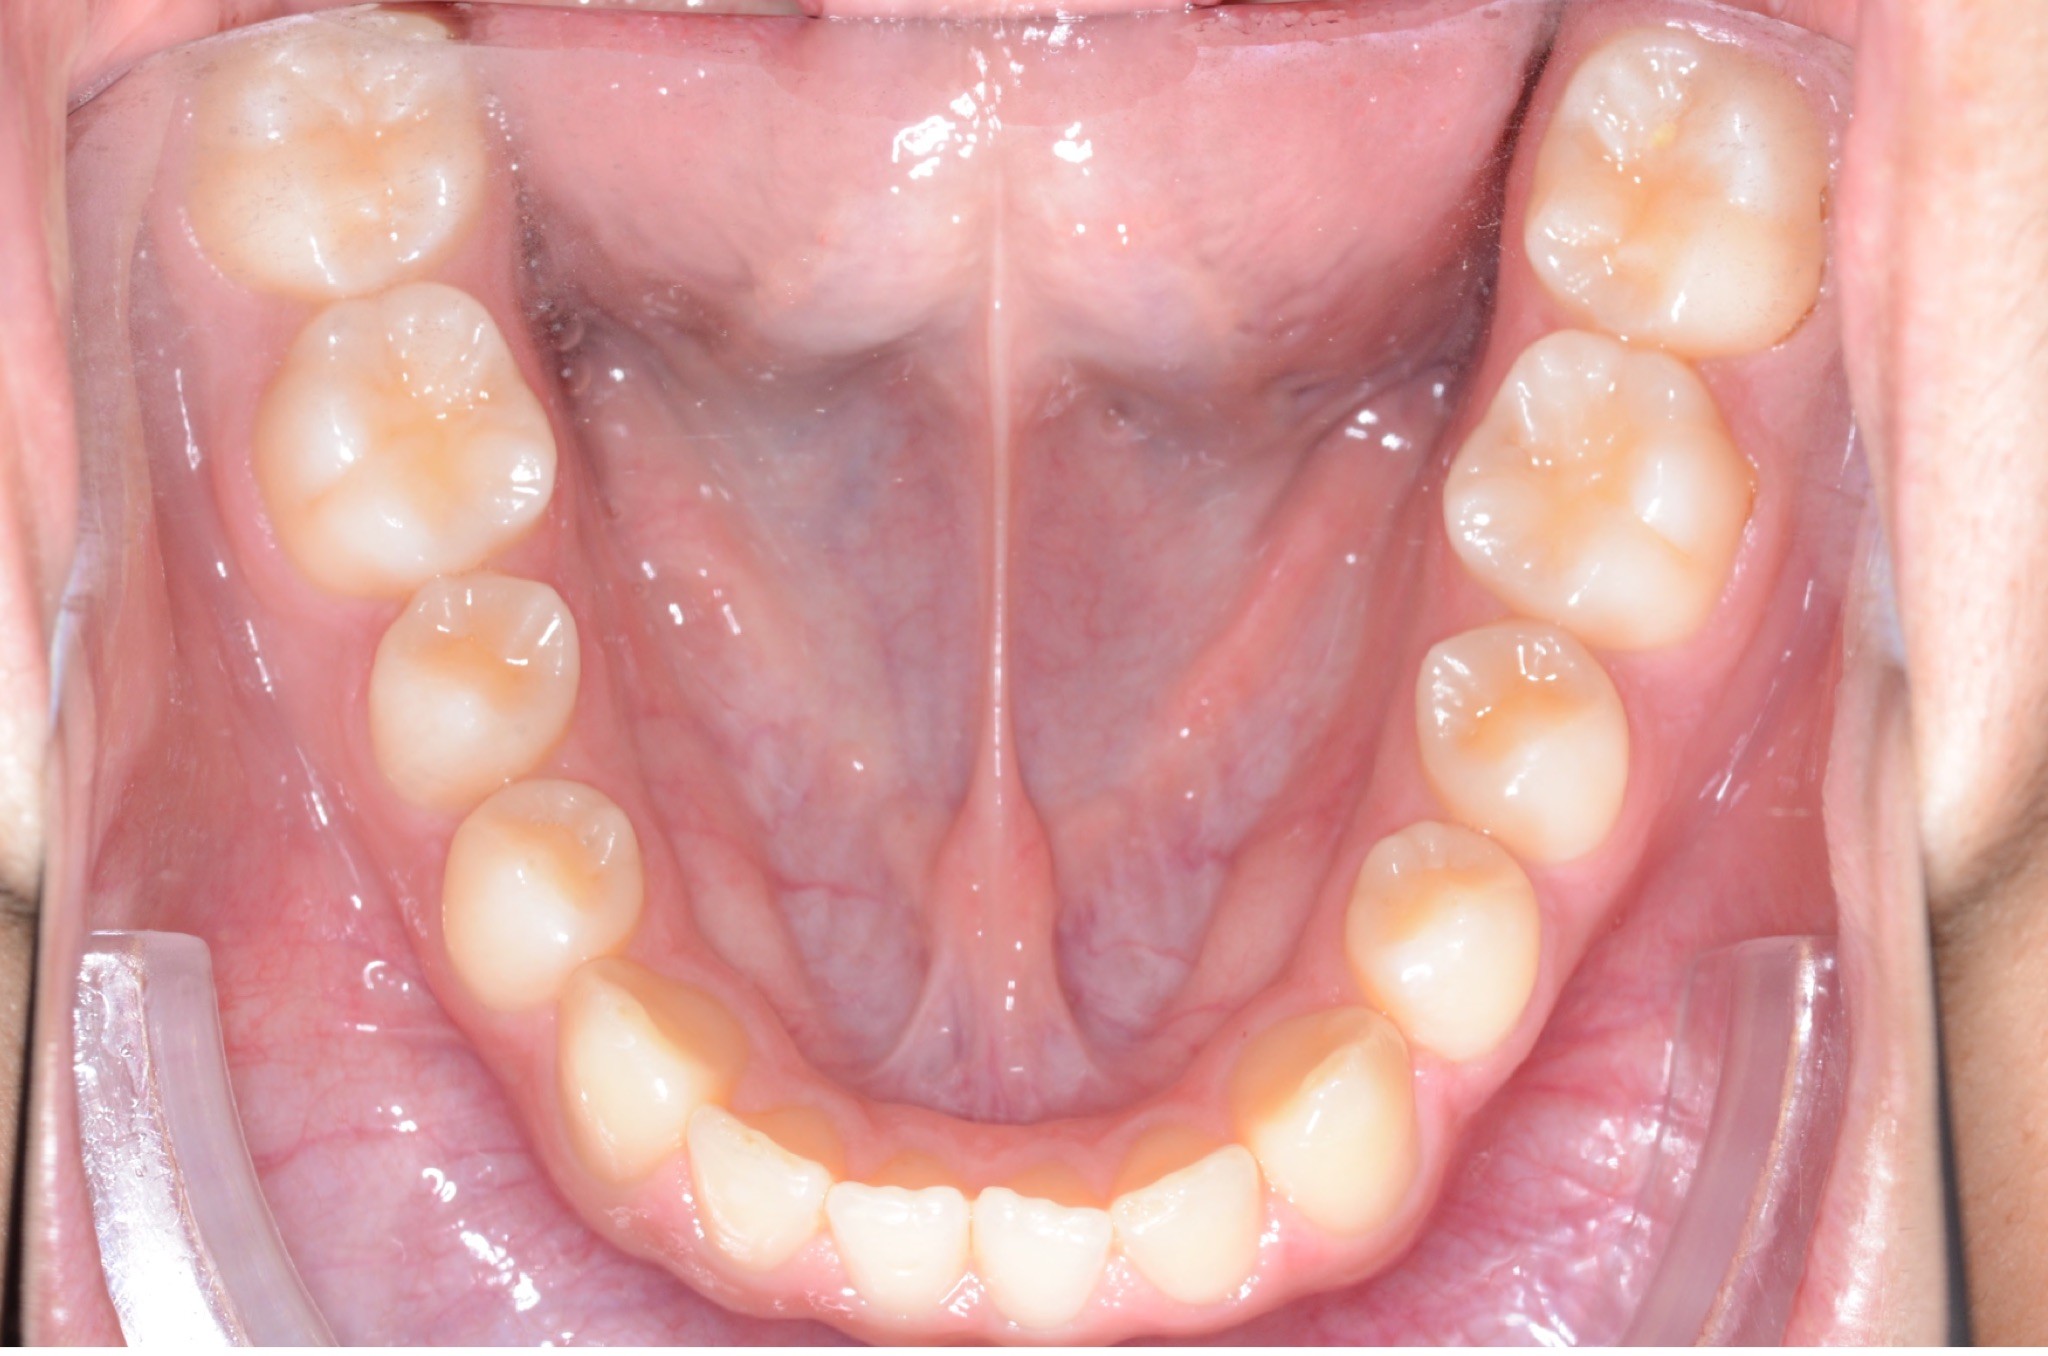

Initial treatment

INTRAORAL